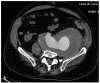

Chronic-contained rupture of an aortic aneurysm is a rare subset of ruptured aneurysms. The presentation is unusual, and the diagnosis is frequently delayed. Here, we describe a case of contained rupture of abdominal aortic aneurysm that presented with signs and symptoms of femoral neuropathy. Clinical and radiological findings were initially misinterpreted. The correct diagnosis was formulated belatedly, causing a progressively increased risk of fatal events. Surgical aortic repair was performed and the postoperative course was uneventful. In conclusion, in the presence of a retroperitoneal mass, a diagnosis of chronic-contained rupture of an abdominal aortic aneurysm should be considered.